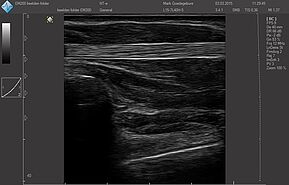

Датчики имеют большую чувствительность и высокое разрешение, благодаря чему обеспечивают максимальное проникновение и улучшают соотношение сигнал /шум. В результате формируется максимально четкая детализированная картинка УЗИ изображения.

- Усовершенствованная технология уменьшения спекл-шумов

- Улучшение изображения